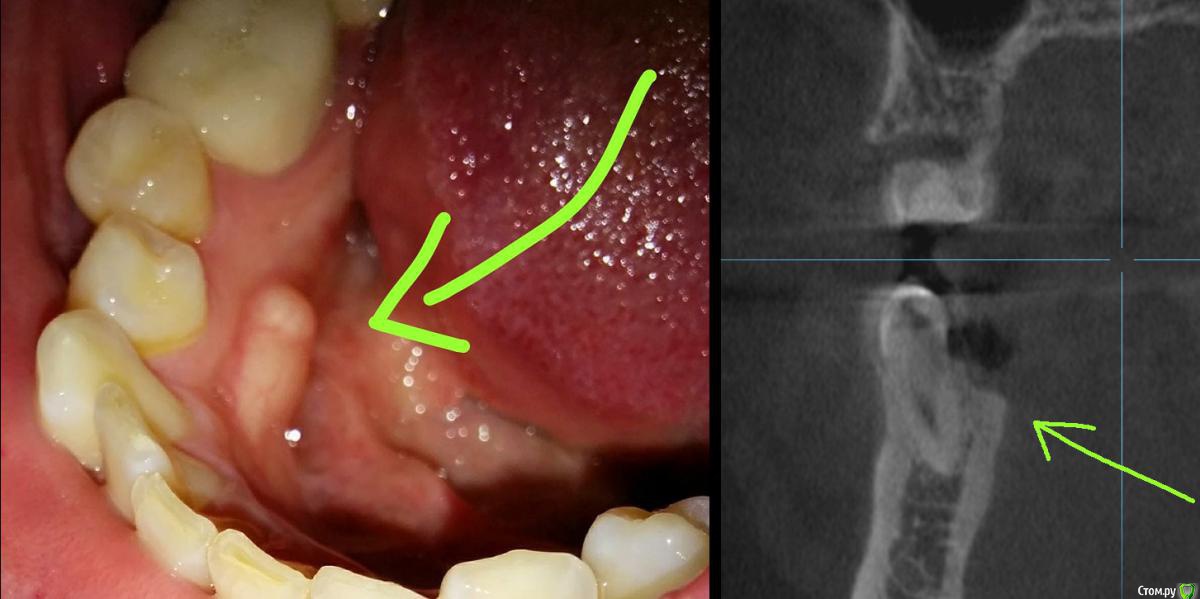

Tot20 Опубликовано 23 августа, 2019 Поделиться Опубликовано 23 августа, 2019 (изменено) Здравствуйте, мне нужен ваш совет. На фото моя проблема. Это видимо какой-то костный нарост. Так мне сказали пару лет назад после того как я делал кт. Он не болит. На ощупь твёрдый.Зубы рядом - живые, зубы не болят. Сейчас этот нарост стал крупнее, раньше он был поменьше. А впервые его я заметил лет 5-7 назад. Что это? Как оно называется в медицинской терминологии? Стоит ли беспокоится? Изменено 23 августа, 2019 пользователем Tot20 Ссылка на комментарий

Tot20 Опубликовано 23 августа, 2019 Автор Поделиться Опубликовано 23 августа, 2019 (изменено) Фото Изменено 23 августа, 2019 пользователем Tot20 Ссылка на комментарий

red_butler Опубликовано 23 августа, 2019 Поделиться Опубликовано 23 августа, 2019 Это экзостоз, не парьтесь, считайте это костью про запас))) 2 Ссылка на комментарий